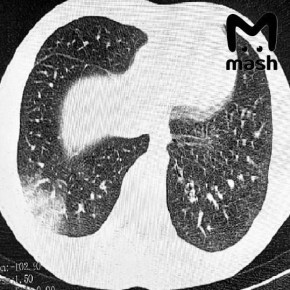

Подростки в тяжёлом состоянии, одному пришлось делать операцию на лёгких.У 16-летнего пациента — серьёзная дыхательная недостаточность, потребовалась искусственная вентиляция лёгких. У другого — двусторонняя вейп-ассоциированная пневмония EVALI, врачи...

Статистикой за последние полгода поделился Минздрав РО. Пациентов привозили тяжёлыми, одного сразу положили на ИВЛ. Другому потребовалась срочная операция — у него развилась двусторонняя вейп-ассоциированная пневмония (EVALI). Всех спасли.Подписывайся...